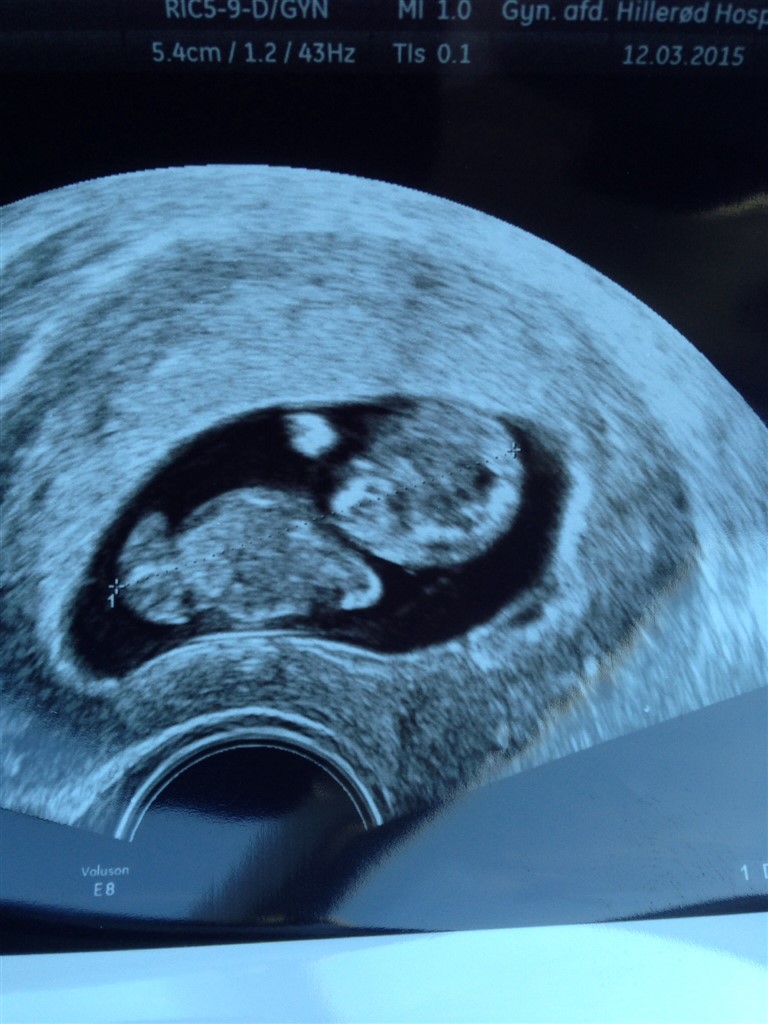

10+3 og 4 cm livlighed

Har i dag været til scanning på gyn.amb. som led i det kontrolforløb jeg har været i efter min mola før jul. Med hjertet i halsen som de andre gange, lagde jeg mig på briksen til en indvendig scanning... Og tak skal du have en lille livlig Spunk der sprællede for fuld hammer  Jeg er så glad, og lettet over at alt mod alle odds, er helt perfekt og jeg nu kan følge et normalt svangerforløb